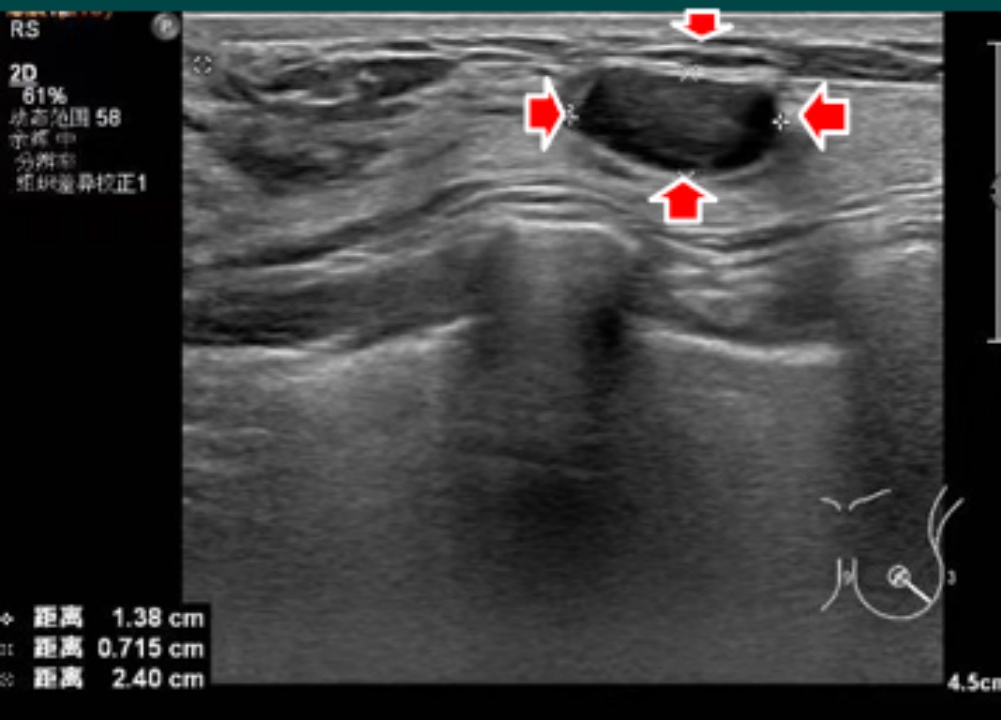

超声提示:右乳低回声结节,边界清,形态规则(考虑纤维腺瘤)